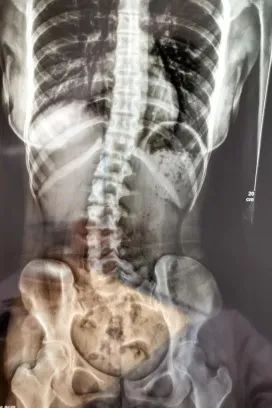

18岁的小邹姑娘,在学习久坐后会常常出现腰痛,脖子伏案久了会有一点酸,近期酸痛情况逐渐严重,遂来到广医三院中医科就诊。经过x光检查发现其腰椎向右侧弯、旋转,并以腰2椎体为中心向右侧弯,Cobb角约10°,脊柱向右发生明显侧弯。  小邹的脊柱明显侧弯